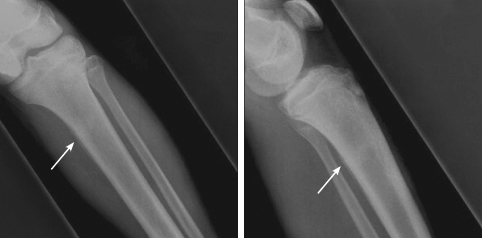

Anteroposterior and lateral views of the tibia and fibula are shown

The radiographs show periosteal new bone formation along the posterior aspect of the proximal shaft of the tibia. Sclerosis is visible transversely across the proximal diaphysis of the tibia.